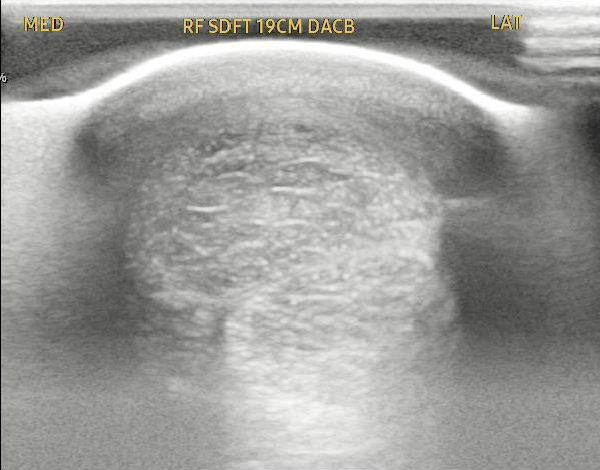

Case Study 2 – Equine Tendon Regeneration

The attached images show a pre- and post-treatment equine superficial digital flexor tendon injury.

This horse received two injections spaced one month apart and at the 2 ½ month point has produced a reduction in the core tendon lesion of approximately 70%.

Source: Temecula Creek Equine